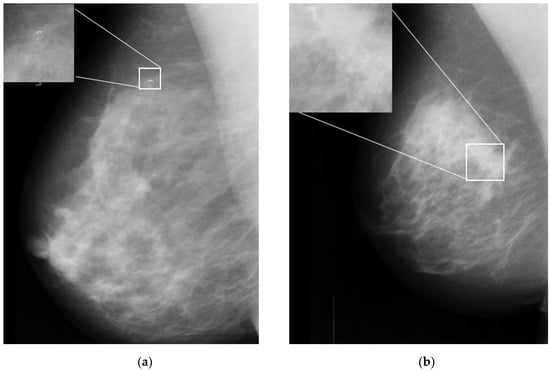

One of the important signs in cancer detection on mammographic images is the presence of microcalcifications, which appear as small bright spots within an inhomogeneous background [6]. Figure 1a,b illustrates an example of benign and malignant microcalcifications on mammogram images taken from the MIAS database [7]. Note that the morphology of this microcalcification is a crucial predictor of its pathological nature. Large, round, and oval calcifications of uniform size exhibit benign (non-cancerous) characteristics. In contrast, smaller and non-uniform calcifications exhibit characteristics of malignant growth [8,9]. In clinical practice, it is difficult and time-consuming for radiologists to interpret and evaluate microcalcifications accurately. This is true especially when the microcalcifications appear in low contrast and are obscured by the background tissue of the images [10]. Here, human errors based on subjective evaluations may lead to unnecessary biopsy procedures, which can cause harm and anxiety for patients [11].

Figure 1.

Sample microcalcification on mammogram images in the MIAS dataset [7]. (a) Benign microcalcifications and (b) malignant microcalcifications.